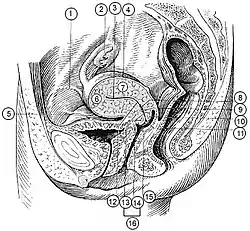

Median sagittal section of female pelvis. (Rectouterine excavation labeled at center left.) | |

The rectouterine pouch (recto-uterine pouch, pouch of Douglas, or rectovaginal pouch) is the extension of the peritoneum into the space between the posterior wall of the uterus and the rectum in the human female.[1]

In women, the rectouterine pouch is the deepest point of the peritoneal cavity. It is posterior to the uterus, and anterior to the rectum.[2] Its anterior boundary is formed by the posterior fornix of the vagina.[1] The pouch on the other side of the uterus near to the posterior fornix is the vesicouterine pouch.

After passing over the fundus of the uterus, the peritoneum extends inferiorly along the entire posterior aspect of the uterus, reaching the posterior vaginal wall before reflecting superior-ward onto the anterior aspect of the rectal ampulla (i.e. the inferior portion of the rectum).[3]

In men, the region corresponding to the rectouterine pouch is the rectovesical pouch, which lies between the urinary bladder and rectum.